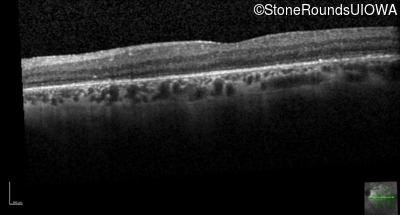

Age at visit: 57 years